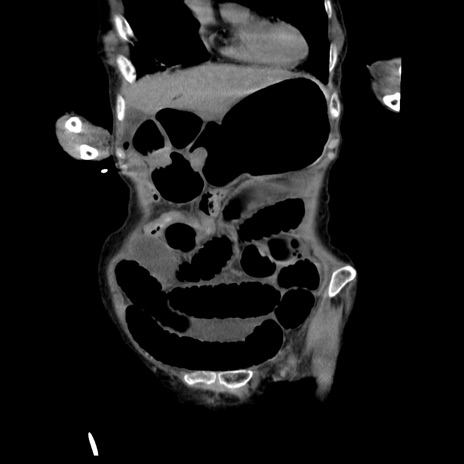

横断像